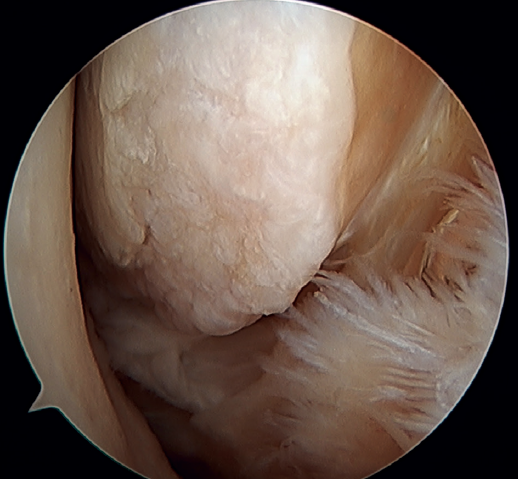

The main indication for this repair is rupture of the upper fascicle of the ATFL from its fibular insertion, with good tissue quality of the remaining ligament (Figure 3).

Figure 3. A: identification of the fibular insertion of the ATFL (*) with excellent quality of the tissue remnant; B: technique with two knotless implants and using a modified single anterolateral portal; C: final result. P: fibula; T1: talofibular tunnel; T2: calcaneofibular tunnel.